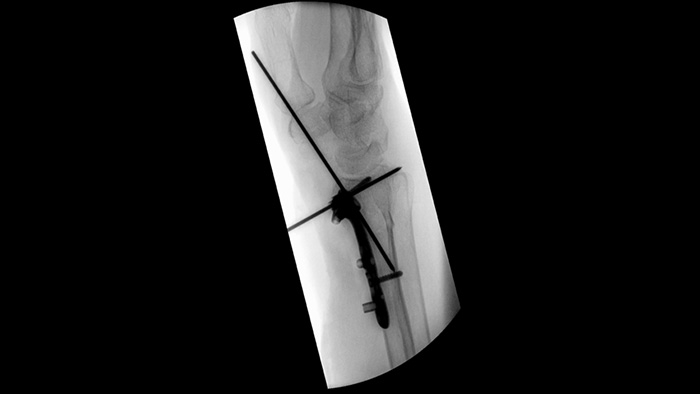

Al configurar tornillos pediculares para una artrodesis vertebral o la reparación de fracturas, reducir las distracciones y las discusiones técnicas puede ayudar a los equipos quirúrgicos a mantenerse enfocados en los pacientes. Con las ayudas de navegación del flujo de trabajo de Unify, los equipos quirúrgicos experimentaron interacciones más fluidas y menos falta de comunicación en un estudio de usabilidad.1

Simplifique el flujo de trabajo para casos ortopédicos desafiantes que requieran un reposicionamiento frecuente del arco en C móvil. Con la memoria de posición,2 los participantes en un estudio de usabilidad1 lograron un reposicionamiento correcto del 94 % a la primera vez y experimentaron menos frustración durante las tareas de (re)posicionamiento.